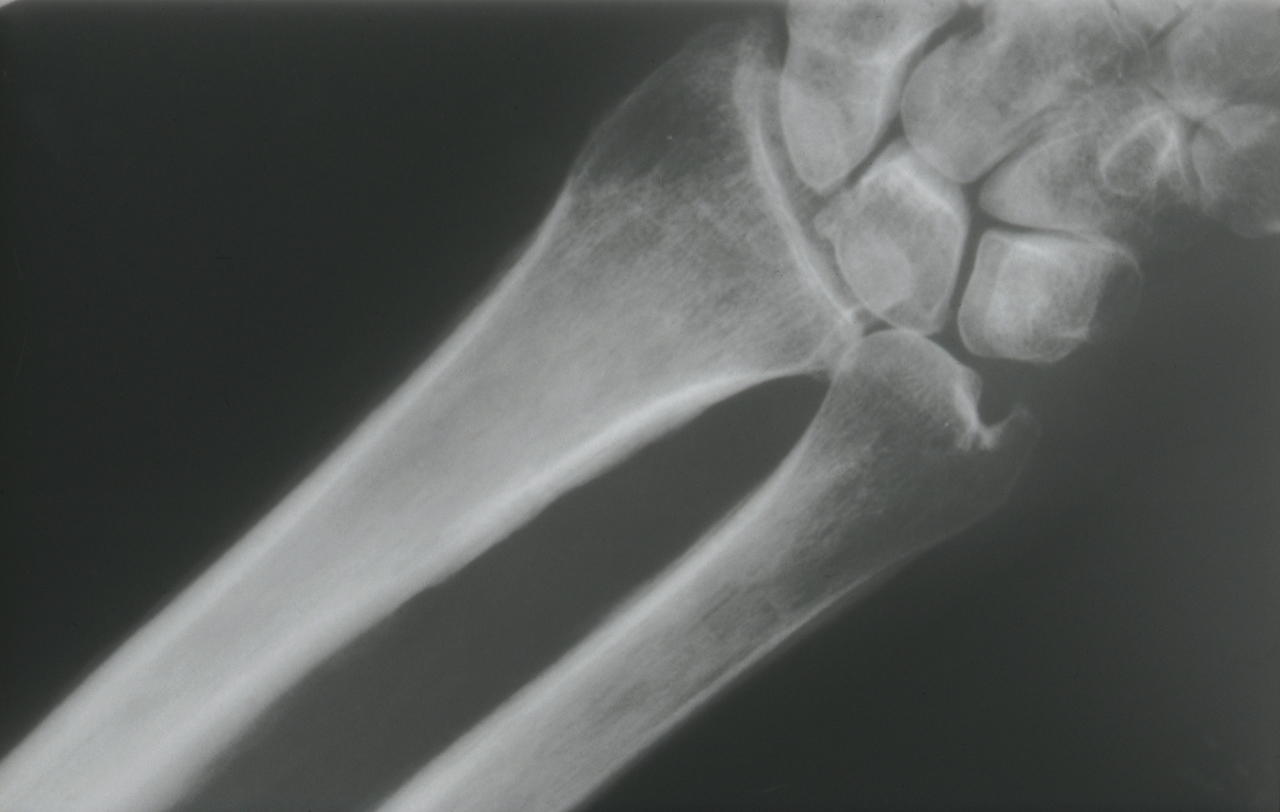

Quel est votre diagnostic ? Ostéomyélite Maladie de Paget Infarctus osseux Ostéo-arthropathie hypertrophiante Il s'agit d'une ostéo-arthropathie hypertrophiante. Myélome OK Valider mes réponses